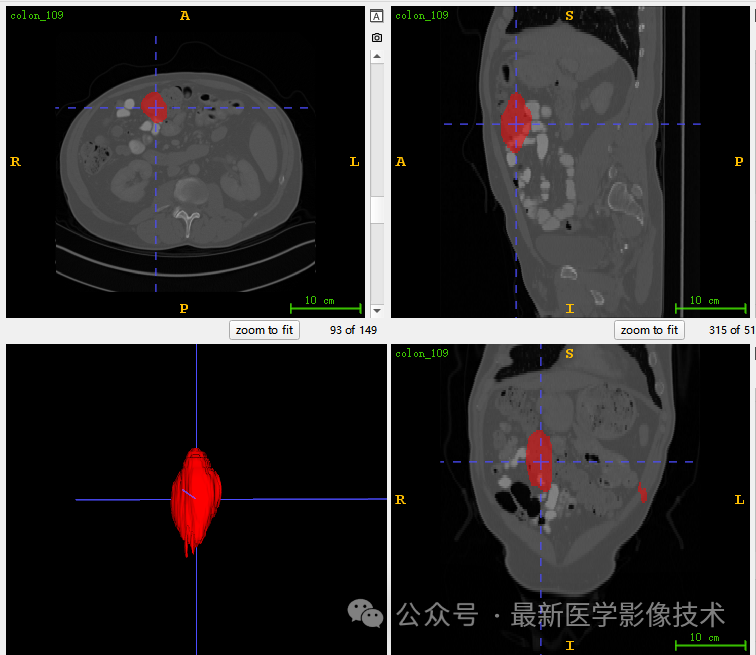

5、验证集分割结果

左图是金标准结果,右图是预测结果。